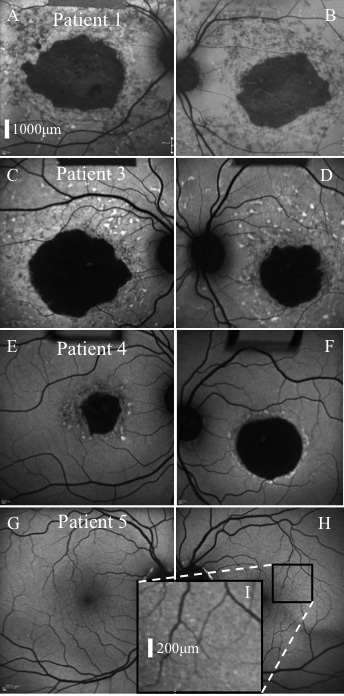

Figure 2. Fundus autofluorescence.

Representative images of affected patients 1 (A, B),

3 (C, D), 4 (E, F), and unaffected

patient 5 (G, H, I) are presented. Image I

corresponds to the black square region in image H.

Geographic atrophy was a prominent feature of Stargardt disease

in the three affected patients, with widespread focal fundus

autofluorescence (FAF) abnormalities observed in patients 1 and

3 also. Images of patient 5 revealed sparse discrete

hyperautofluorescent macular lesions bilaterally. All subjects

exhibited peripapillary sparing on FAF imaging. A corresponding

size bar for images A-H is included in A.

A size bar for I is included within the image.